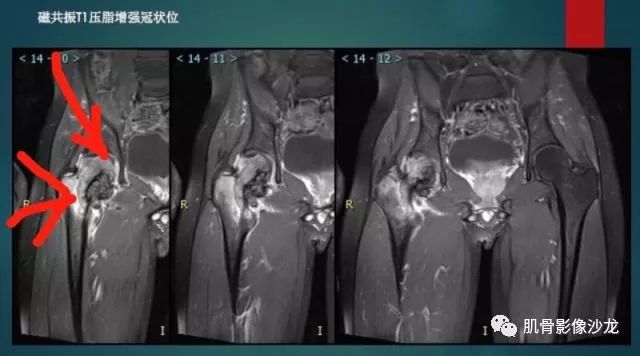

葛英霖 20:37 明显侵蚀骨内膜啊,硬化边也不完整 (细箭头所示)

Echo 20:39 葛老师是指这些地方么?

葛英霖 20:5 4 常规纤维类的多一些,冠状位没有看到明显脂肪。纤维结构不良、纤维组织细胞瘤、软粘纤之类。

夏威夷的风 20:58 强化渐进性强化吧 边界清晰 里面也见线状低信号

Echo 21:04 总之这例就是各位老师说的硬化边明显,没有软组织肿块,没有侵犯,考虑良性病变,增强渐进性强化,所以考虑BFH